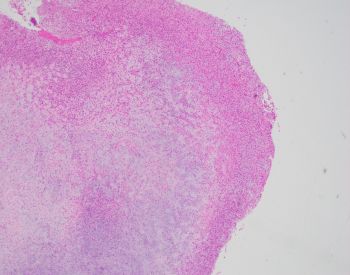

81-year-old female with a remote history of follicular lymphoma was undergoing evaluation for possible disease recurrence when an incidental right breast mass was identified.